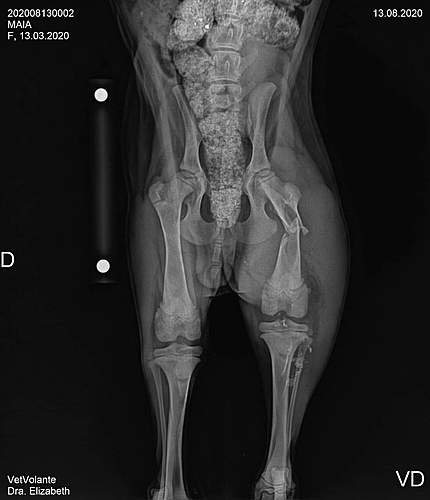

A Maia precisa de ajuda, ela foi atropelada, sofreu uma fratura na bacia e no femuor, precisa urgente de cirurgia. Ela tem dono, são duas crianças, os pais, o felizmente não tem condição que arcar com as despesas da cirurgia. A Maia tem apenas cinco meses, tem uma vida toda pela frente, mas precisa ser operada com urgência. Ela é uma cachorrinha muito dócil e muito carinhosa, as crianças sentem falta dela, é um membro da família. Que Deus abençoe cada um que fizer uma doação, ajudará a salvar a vida de uma cachorrinha.